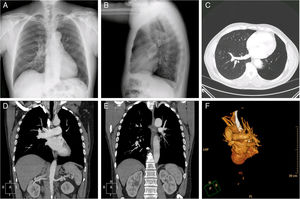

A 67-year-old man, non-smoker, with no other history of interest, consulted due to a long history of progressive dyspnea, mMRC grade II. Chest radiograph was performed (Fig. 1A and B), showing loss of volume in the left lower lobe (LLL) along with hyperlucency and apparent lack of vasculature in that region. Computed tomography (CT) (Fig. 1C–F) showed agenesis of the left lower pulmonary vein and artery along with marked hypoplasia of the left lower lobe and compensatory emphysema of the right upper lobe. Echocardiography revealed no changes or signs indicative of pulmonary hypertension.